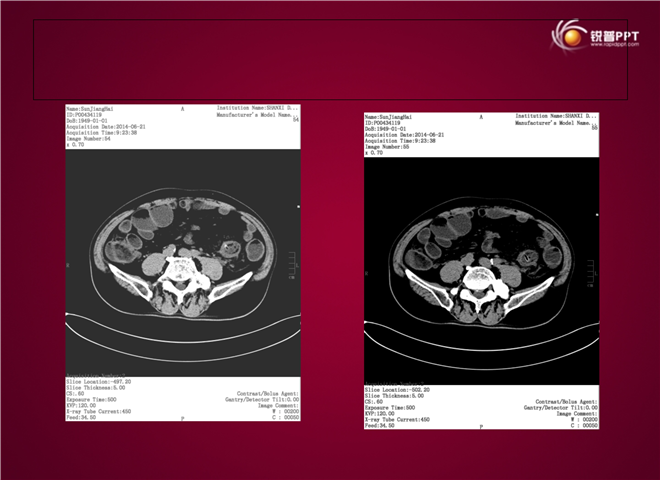

23_CT读片基础